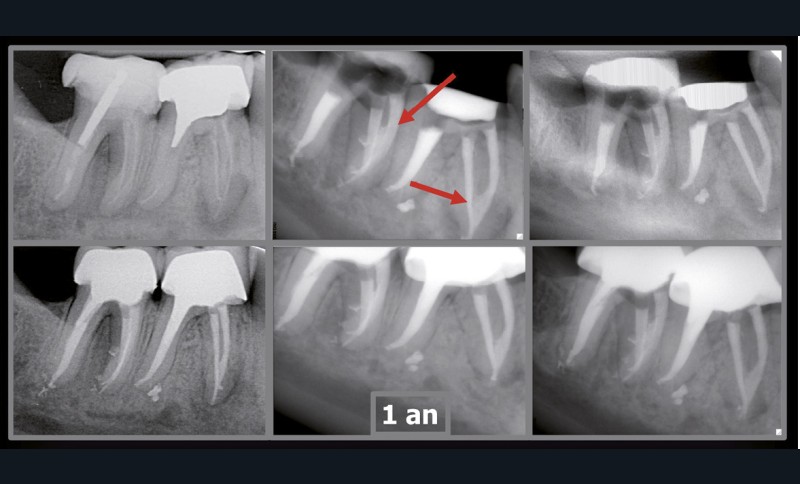

Rebondissant sur l’imagerie 3D et la mise en évidence des anatomies canalaires complexes, Peters, en 2001, décrit l’insuffisance instrumentale dans le traitement endodontique, et montre que 35 % des surfaces sont intactes après préparation canalaire correctement menée [18].

Endal, en 2011, montrait également, en utilisant le micro CT Scanner, l’insuffisance de nettoyage des isthmes inter-canalaires à nos techniques conventionnelles [19]. L’utilisation du laser Er:YAG devenait alors incontournable dans le nettoyage de ces isthmes et des zones non instrumentées (fig. 2 et 3).

Si l’étude de Peters [18] nous montre que l’instrumentation laisse 35 % du volume canalaire non instrumenté, Ricucci et Siqueira montrent que la préparation physico-chimique n’élimine que partiellement les tissus nécrotiques à l’entrée des canaux latéraux, des isthmes et des ramifications apicales, en laissant des tissus enflammés et infectés, en association avec des lésions apicales [29] (fig. 4 et 5).

Fig. 4 – Coupe d’une racine mésiale de molaire mandibulaire avec deux canaux traités. Coupe à 3 mm de l’apex, coloration Brown et Brenn, technique modifiée par Taylor. Ces images montrent un isthme étroit avec une infection bactérienne, ce qui prouve l’importance de désinfecter et d’inclure l’isthme dans les traitements conventionnels et dans les rétropréparations apicales en chirurgie endodontique.

Si les isthmes sont particulièrement mis en évidence au niveau des molaires mandibulaires, cela devient médicalement important au niveau des molaires maxillaires.

La diffusion bactérienne et de leurs toxines, au niveau des molaires maxillaires est à l’origine d’un grand nombre de sinusites maxillaires chroniques, d’origine dentaire. Celles-ci sont principalement causées par l’absence de traitement du deuxième canal MV, qui existe dans 90 % des cas, et il est à noter que ces deux canaux – MV1 et MV2 – sont également reliés par un isthme.

Le nettoyage des isthmes intercanalaires reste un réel problème, et semble responsable de nombreux échecs [43]. Par ailleurs, il est nécessaire d’utiliser des instruments qui évitent de propulser les débris, tant apicalement que latéralement, en obturant les entrées isthmiques avec des débris compactés.